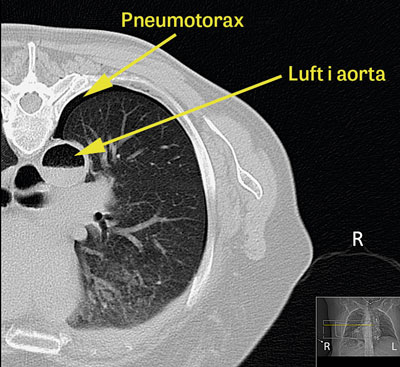

Eftersom patienten fortfarande befann sig i dator­tomografen utfördes undersökning med DT-hjärna/

torax, vilken visade multipla lågattenuerande förändringar i höger hjärnhemisfär, vilka initialt tolkades som fettembolier (Figur 1). Eftergranskning av bilderna från DT-torax visade betydande mängder luft i aorta (Figur 2), vilket dock inte sågs initialt.

Figur 2 (patient 1). DT-torax klockan 10.50 visar betydande mängd luft i aorta med vätskenivå och minimal högersidig pneumotorax. Patienten låg i bukläge under lungbiopsin.